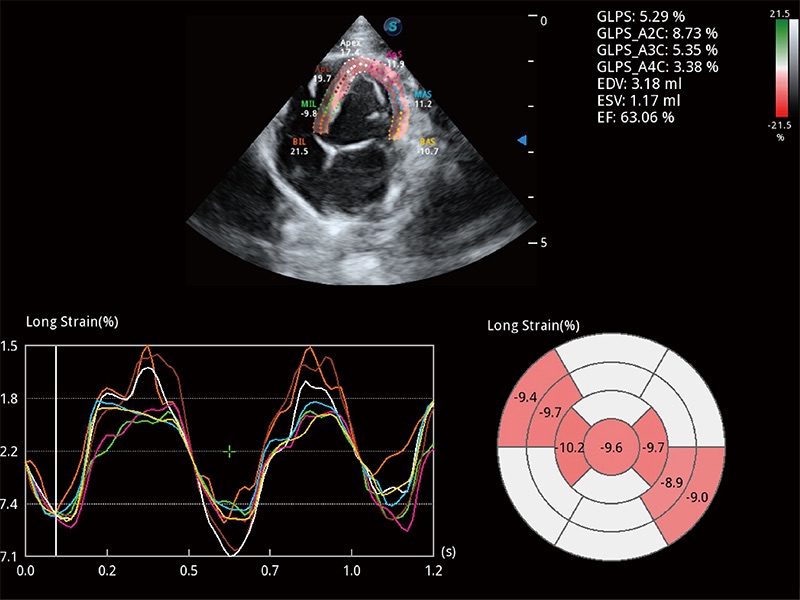

通過(guò)心肌識(shí)別技術(shù)與二維斑點(diǎn)追蹤技術(shù)相結(jié)合,對(duì)心臟的超聲圖像進(jìn)行量化分析。計(jì)算心肌17個(gè)節(jié)段的應(yīng)變、應(yīng)變率、速度、位移等,并通過(guò)牛眼圖的形式進(jìn)行呈現(xiàn)。